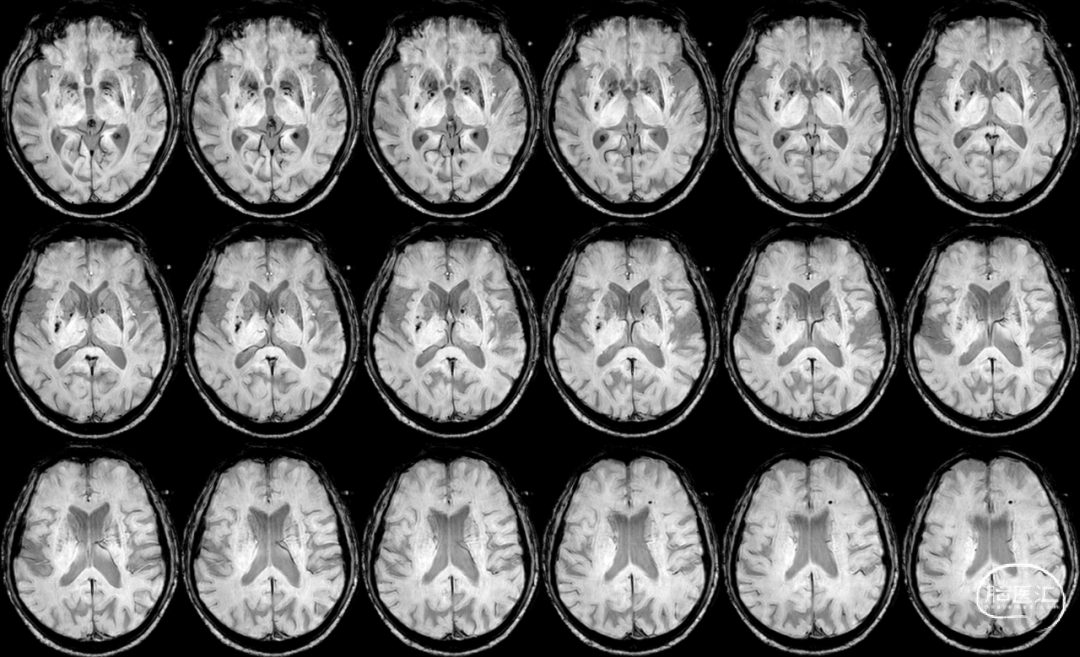

Cranial SWI:SVS+AHVs RMCA M1长条血栓。

T2 Flair:丰富的高信号血管征(HVS)。

Reexamination Cranial SWI:壳核后部,造影剂渗出最多的地方再灌注损伤。